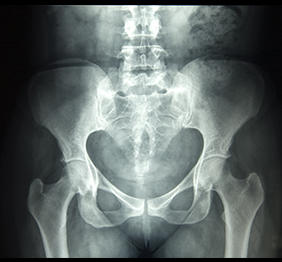

Histerosalpingografie

Este o investigatie imagistica destinata in principal femeilor cu probleme de fertilitate. Prin acesta metoda se poate explora intr-un mod indirect interiorul cavitatii uterine, precum si permeabilitatea trompelor uterine, contribuind la stabilirea cauzei infertilitatii.